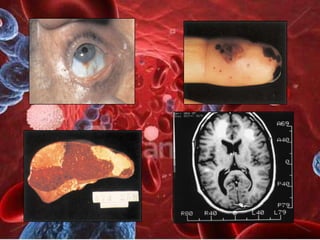

Vegetaciones endocardíticas

Embolismo

Área      pulpejos

subungueal

hemorra

gias

Lesiones vasculares

Neurológicas               Renales

•   Embolismo cerebral

•   Abceso cerebral

• Insuficiencia renal

•   Aneurismas micóticos

(glomerulonefritis)

•   Encefalopatía tóxica   • Embolismo renal

•   Meningitis               (HTA + hematuria)

Neurológicas Renales • Embolismo cerebral • Abceso cerebral • Insuficiencia renal • Aneurismas micóticos (glomerulonefritis) • Encefalopatía tóxica • Embolismo renal • Meningitis (HTA + hematuria)

TROMBOSIS DE VÁLVULA PROSTÉSICA MECÁNICA ´CAL CALCIFICACIÓN CON DESGARRO SEGUNDARIO DE UNA VÁLVULA CARDIACA BIPROSTÉSICA